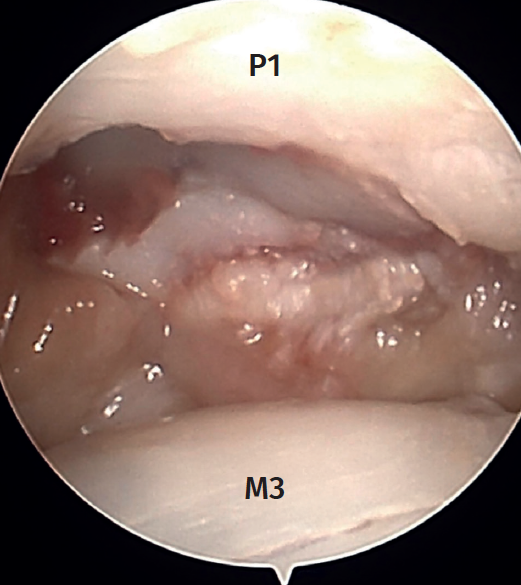

Arthroscopy of the MCP joint allows extensive visualization of the metacarpal head and the base of the proximal phalanx (Figure 1).

In the case of the thumb and sometimes on the radial side of the index finger, we can visualize the sesamoid bones. The radial and ulnar collateral ligaments as well as the accessory ligaments in a more volar position are clearly visible in all the fingers(1). The trajectory of the ligaments can be followed to their origin on both sides of the metacarpal head(2). The insertion of the ligaments at the base of the proximal phalanx is often injured after trauma, and we therefore must be able to identify this.

To follow a reproducible systematic approach, we can start by visualizing the side opposite to where the arthroscope is inserted, i.e., the contralateral collateral ligament, and then assess the volar plate, identify the sesamoid bones (if any), the ipsilateral ligament, and finally the dorsal capsule. The metacarpal head and the base of the proximal phalanx are then assessed, followed by the synovial recesses and the origins of the collateral ligaments.